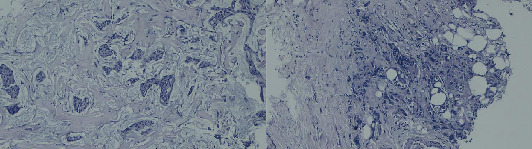

多发原发恶性肿瘤(MPMNs)是指同一个体出现两个或多个不同的肿瘤。同时发生的乳腺癌和结肠癌并不常见,由于缺乏标准化的指南,这给管理带来了挑战。我们报告一位73岁的女性右乳肿块,随后被诊断为2级浸润性导管癌。CT偶然发现右结肠壁增厚,结肠镜活检证实为中分化浸润性腺癌。在新辅助化疗后,她同时接受了根治性乳房切除术、腋窝淋巴结清扫术和右半结肠切除术。术后恢复顺利。辅助放化疗是根据多学科小组(MDT)建议进行的。同步乳腺癌和结肠癌对诊断和治疗计划提出了独特的挑战。MDT合作对于这些复杂病例的个性化治疗策略和优化结果至关重要。

Multiple primary malignant neoplasms (MPMNs) are defined as two or more distinct tumors in the same individual. Synchronous breast and colon cancers are infrequent and present management challenges due to the lack of standardized guidelines. We report a 73-year-old woman presenting with a right breast mass, subsequently diagnosed as Grade 2 invasive ductal carcinoma. Staging CT incidentally revealed right colon wall thickening, and colonoscopy with biopsy confirmed moderately differentiated invasive adenocarcinoma. Following neoadjuvant chemotherapy, she underwent simultaneous radical mastectomy with axillary lymph node dissection and right hemicolectomy. Postoperative recovery was uneventful. Adjuvant chemoradiation was administered per multidisciplinary team (MDT) recommendation. Synchronous breast and colon cancers pose unique diagnostic and treatment planning challenges. MDT collaboration is crucial for personalized treatment strategies and optimized outcomes in these complex cases.